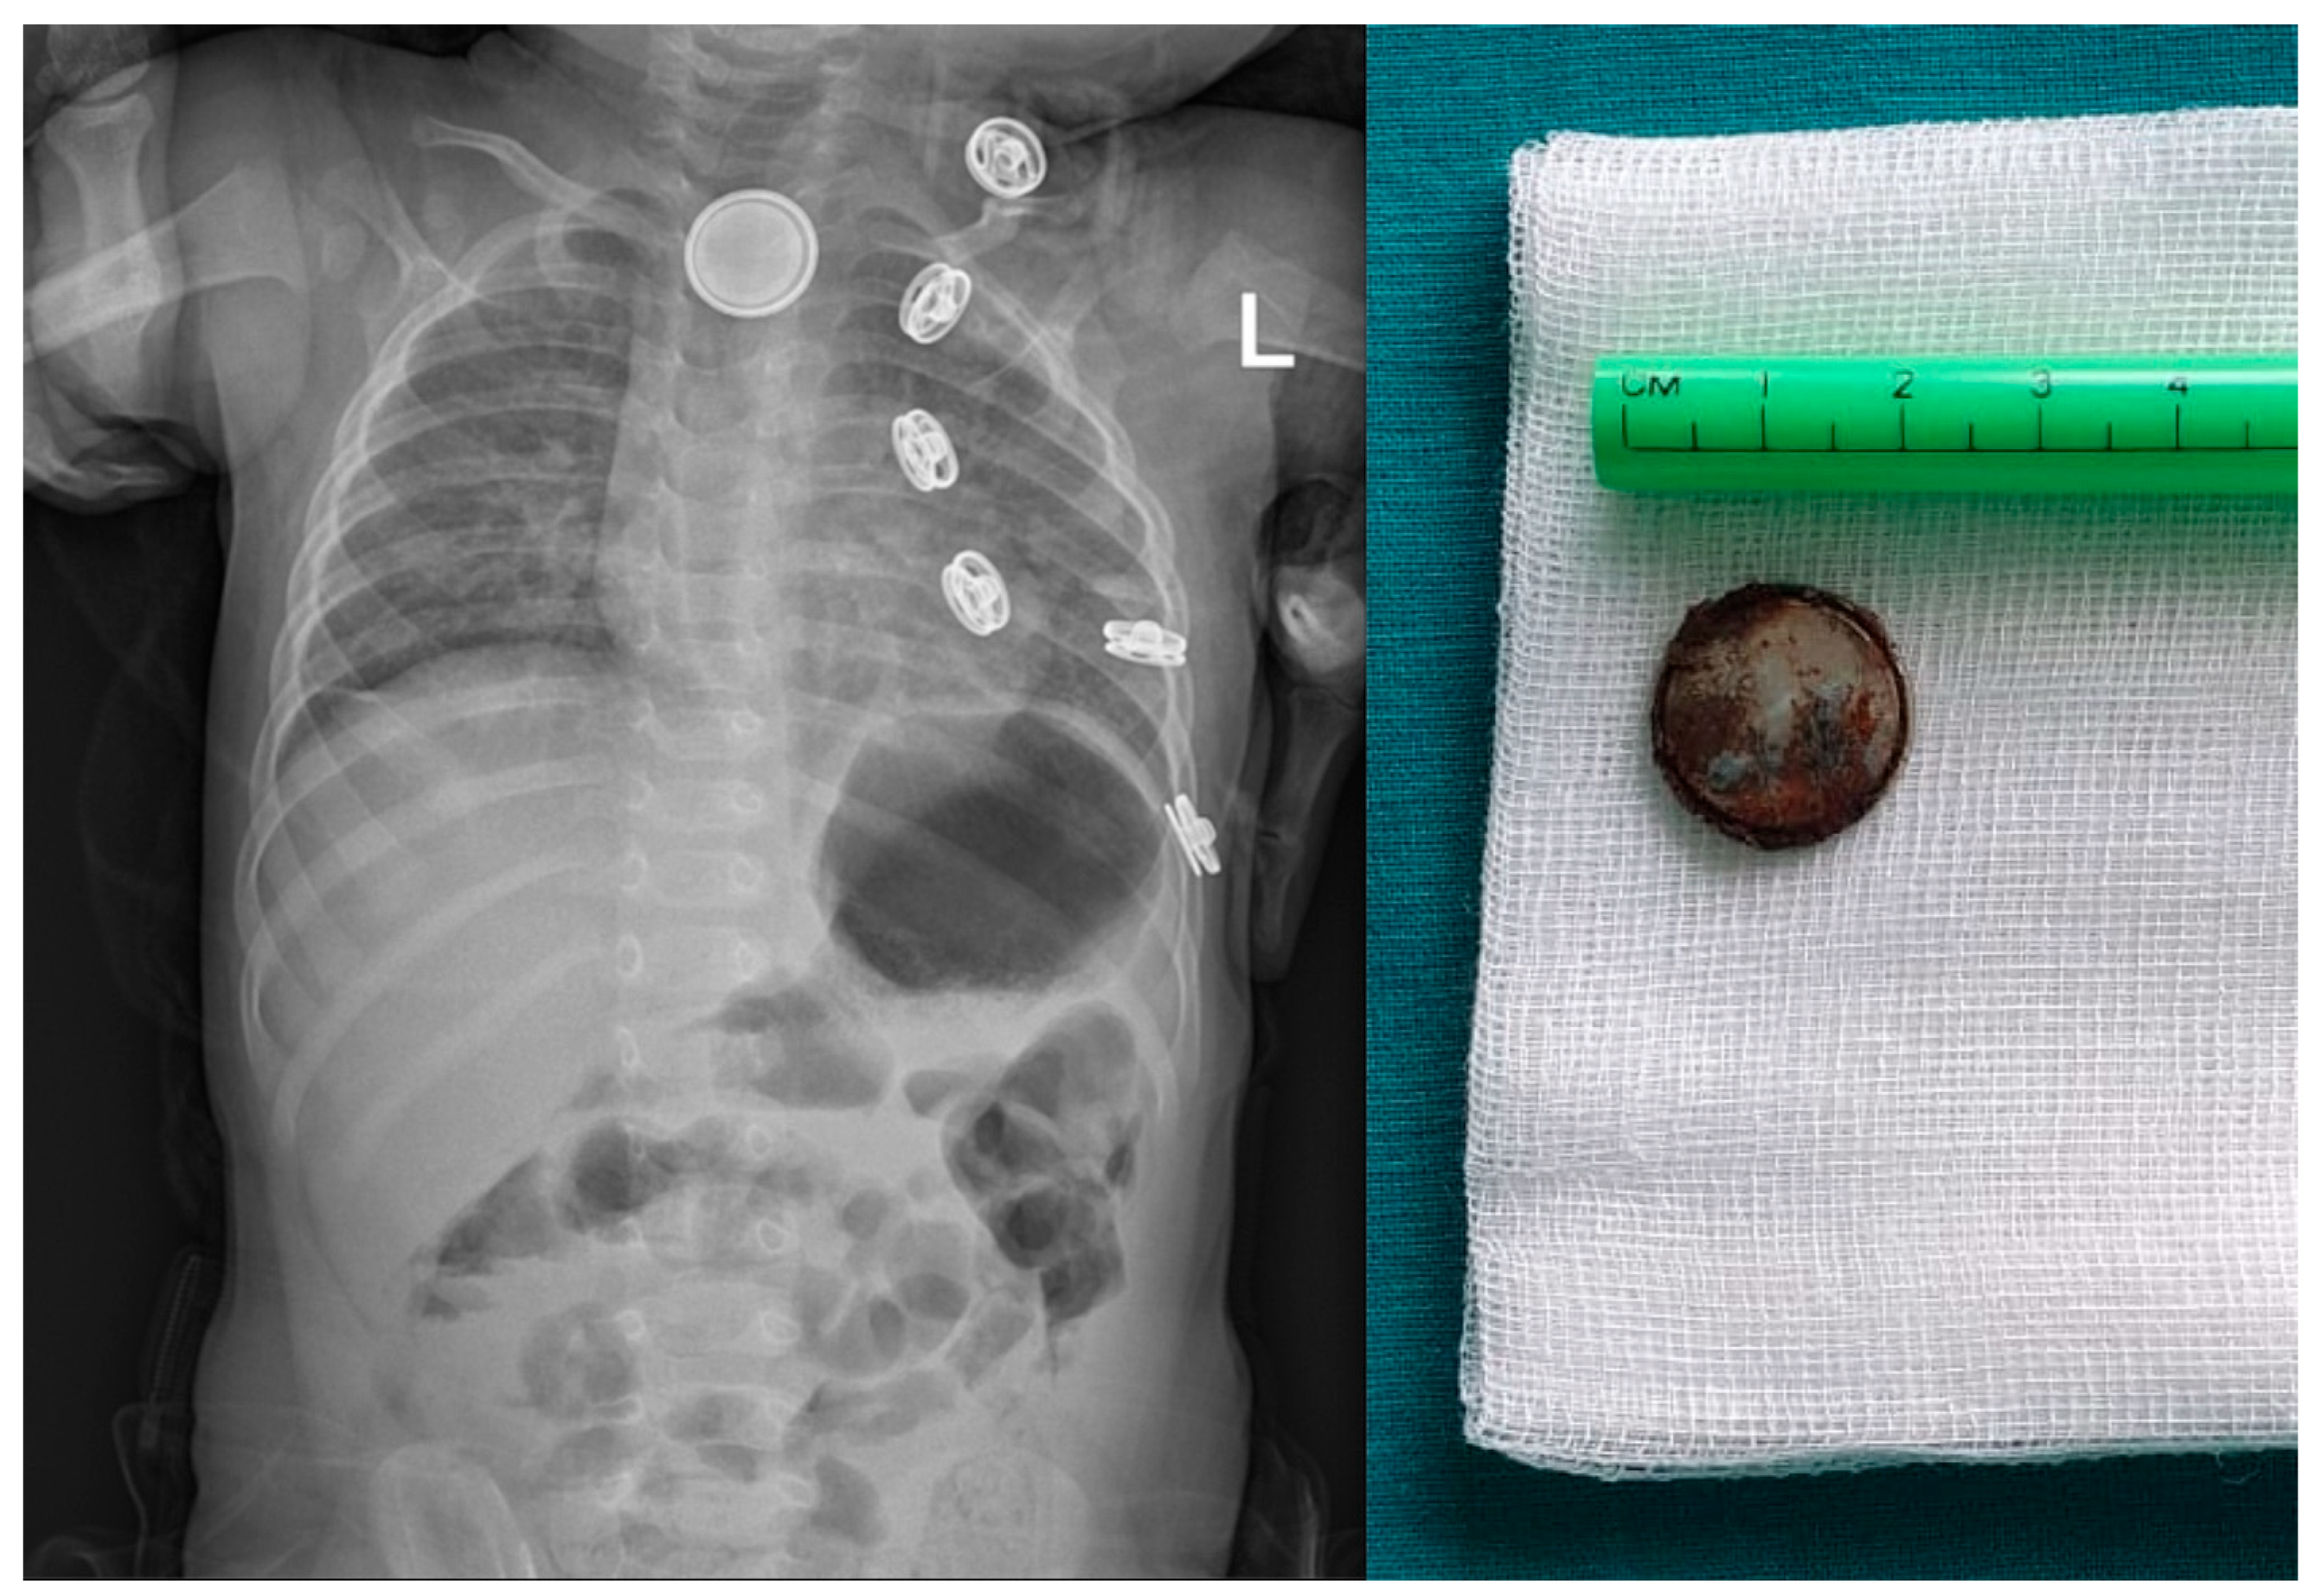

7. Esophageal Foreign Bodies